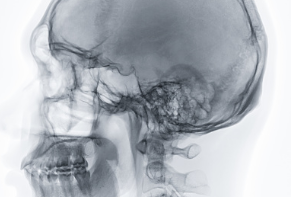

후두신경통은 후두 내부의 신경이 염증이나 손상으로 인해 통증을 일으키는 증상입니다. 이는 목소리 변화, 인후통, 기침, 호흡 곤란 등의 증상을 일으키며, 일상생활에 지장을 줄 수 있습니다.

해부학적인 후두신경통 사진.